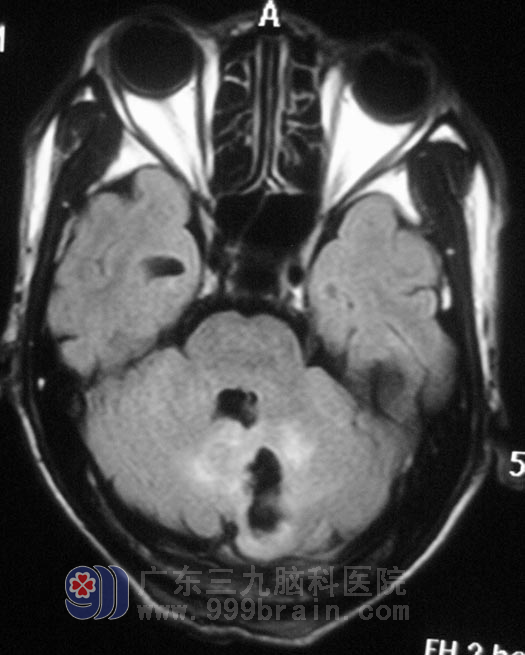

在广东三九脑科医院头颅MR检查提示:1.左侧小脑半球囊性占位性病变;2.小脑扁桃体下疝畸形。行进一步的MR增强检查,囊性强化,鲁明主任考虑囊性星形细胞瘤,不排除血管网织细胞瘤的可能。

2012年1月1日,由综合神经外科 鲁明主任主刀,在全麻下行左侧小脑占位病变切除术+寰枕畸形减压术,术中见淡红色病变组织,与周围边界清楚,血供丰富,沿病灶外侧缘向下分离约2cm见黄色囊液流出。继续沿上缘、下缘、内侧缘完整分离病变,将肿瘤全切除,大小约3cm×4cm×4cm。手术后邓先生一天天病情好转,没再出现天旋地转的感觉,一周后办理出院手续。